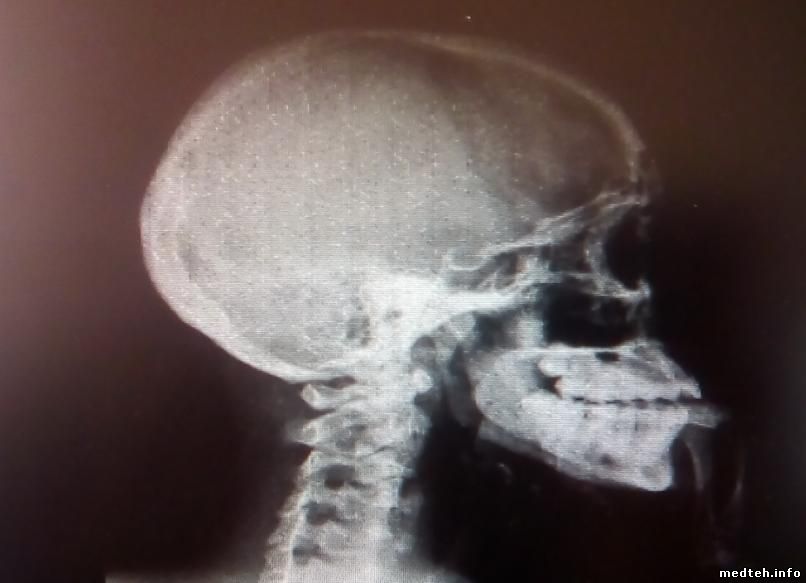

а это шум по всему снимку:

примечательно, что присутствует только 2 вида шума, но они не чередуются, а проявляются в случайном порядке.

вот ещё пара снимков с шумом по всей площади и на правой половине: